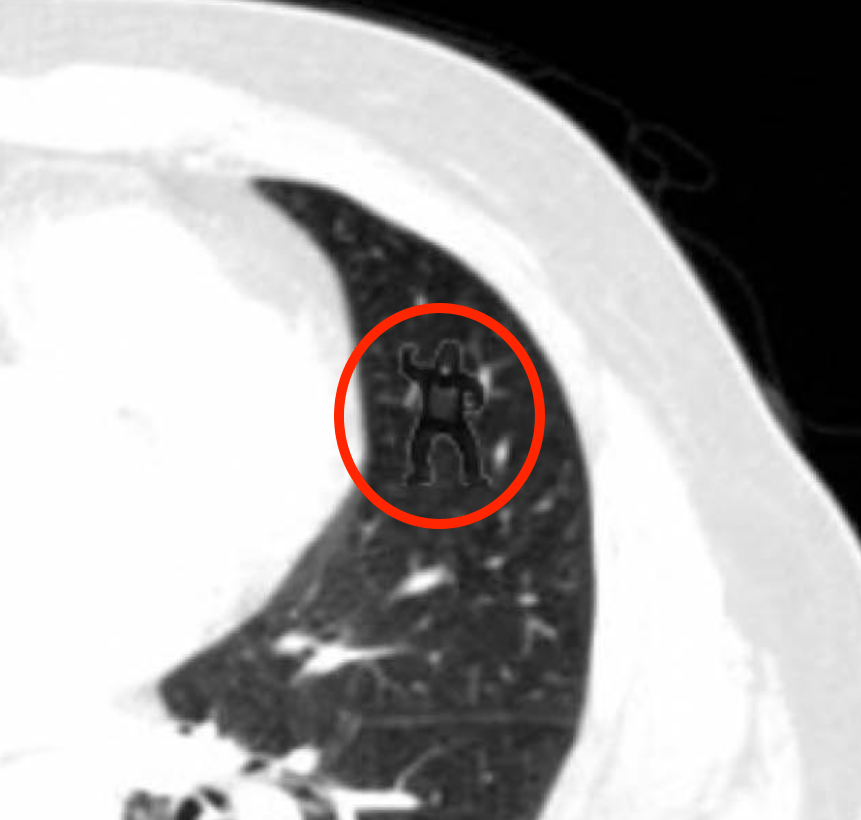

Medicine is a risky business. Sometimes error is avoidable, but some error is intrinsic to the operational practicalities of the delivery of modern healthcare. The missing of a small abnormality on a few slices of a CT scan containing thousands of images is a mode of error genesis that continues despite most radiologists being painfully aware of it. Mitigations to reduce the rate of occurrence (comfortable reporting workstations, absence of interruption, reduced workload and pressure to report, double reporting, perhaps artificial intelligence assistance) are neither infallible nor always operationally realistic. Double reporting halves capacity. While we design processes to reduce risk, it’s impossible to engineer error out completely and other models are needed. To make error productive, we learn from it where we can, but we must recognise that sometimes there is nothing to learn, or that the lessons are so repeated and familiar that it might surprise an independent observer that the error persists (‘never events’ still happen).

(Images from: Drew T, Vo MLH & Wolfe JM. The invisible gorilla strikes again: Sustained inattentional blindness in expert observers. Psychol Sci. 2013 September ; 24(9): 1848–1853)